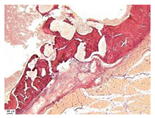

| 3 | ![]() | ![]() | ![]() | ![]() | ![]() |

| 5 | ![]() | ![]() | ![]() | ![]() | ![]() |

| 8 | ![]() | ![]() | ![]() | ![]() | ![]() |